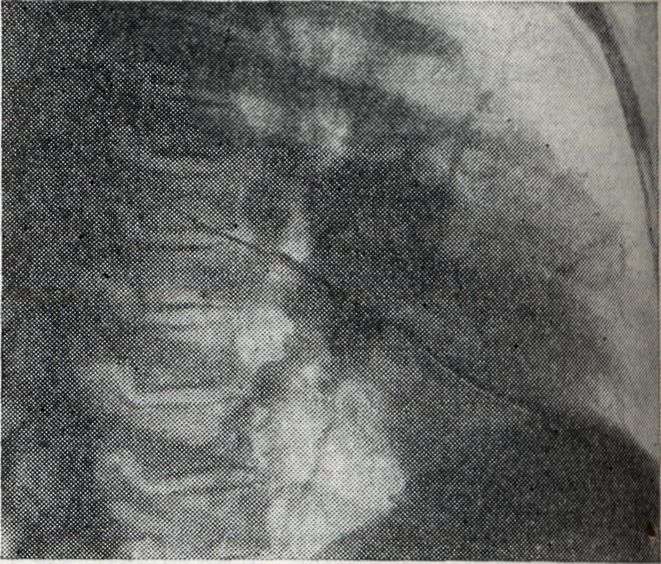

Бронхагенное рассеивание казеозного материала ведёт к развитию тяжёлых бронхопневмоний (лобулярио-казеозных). Осложнения. Течение Б. нередко осложняется плевритом (железисто-плевральный синдром); характерны междолевые экссудативные плевриты (чаще при первичном туберкулёзе). При большом увеличении группы лимф, узлов может возникнуть ателектаз сегмента или доли лёгкого. Длительное существование ателектазов может привести к фибротизации спавшегося участка с образованием бронхоэктазов. Диагноз ставится на основании комплексного клинико-рентгенологического обследования, анамнеза (контакта с туберкулёзным больным), характера туберкулёзной интоксикации. Подтверждением туберкулёзной этиологии процесса в висцеральных грудных лимф, узлах является туберкулиновая проба (см. Туберкулинокагностика). При туберкулёзном Б. чаще встречается резко положительная туберкулиновая проба. При туберкулёзном Б. с тяжёлым осложнённым течением туберкулиновые пробы могут быть слабоположительными (состояние анергии). Выявлению клинически не диагностируемых и осложнённых форм Б. способствует также бронхоскопия (см.), при к-рой нередко обнаруживаются инфильтративные изменения стенки бронха и свищи соответственно расположению патологически изменённого лимф. узла. Основной метод диагностики Б. — рентгенологический. Рентгенодиагностика имеет целью установить наличие увеличенных или уплотнённых висцеральных грудных лимф, узлов. При этом руководствуются принципом целенаправленного рентгенологического исследования области средостения путем применения различных способов послойной рентгенографии (томография лучами повышенной жесткости с продольным, поперечным и косым направлением размазывания теней, с выделением толстых слоев — зонография). Послойная рентгенография должна быть многопроекционной (см. Полипозиционное исследование). Особенно ценнов диагностике поражений труднодоступных для выявления групп лимф. узлов (бифуркационных, левых трахео-бронхиальных, парааортальных, артериального протока, бронхо-пульмональных) использование не только прямых и боковых, но и косых проекций с поворотом грудной клетки на 45° в правом и левом лопаточном положении. На послойных рентгенограммах выявляются сочетанные поражения бронхов и лимф, узлов, а в отдельных случаях — лимфо-бронхиальные свищи и компрессионные стенозы. При опухолевидной форме Б. перифокальные явления в прилегающей лёгочной ткани обычно отсутствуют. Тень корня увеличена, менее структурна, отдельные сосудистые стволы корня плохо различимы (рис. 1). Проекции бронхов менее отчётливы, тень корня почти сливается с тенью средостения. Наружная волнообразная или бугристая граница деформированного корня проецируется в виде отчётливой, хотя и не всегда резкой линии, что зависит от отсутствия или наличия воспалительных изменений в капсуле лимф, узлов. При одностороннем опухолевидном Б. изменения корня противоположного лёгкого менее выражены (рис. 2), на стороне поражения лёгочный рисунок несколько усилен, прилежащие листки междолевой плевры уплотнены (рис. 3). При вовлечении в процесс медиастинальной плевры бугристые наружные контуры корня или средостения могут исчезать. Тень средостения расширена, имеет гладкие контуры.